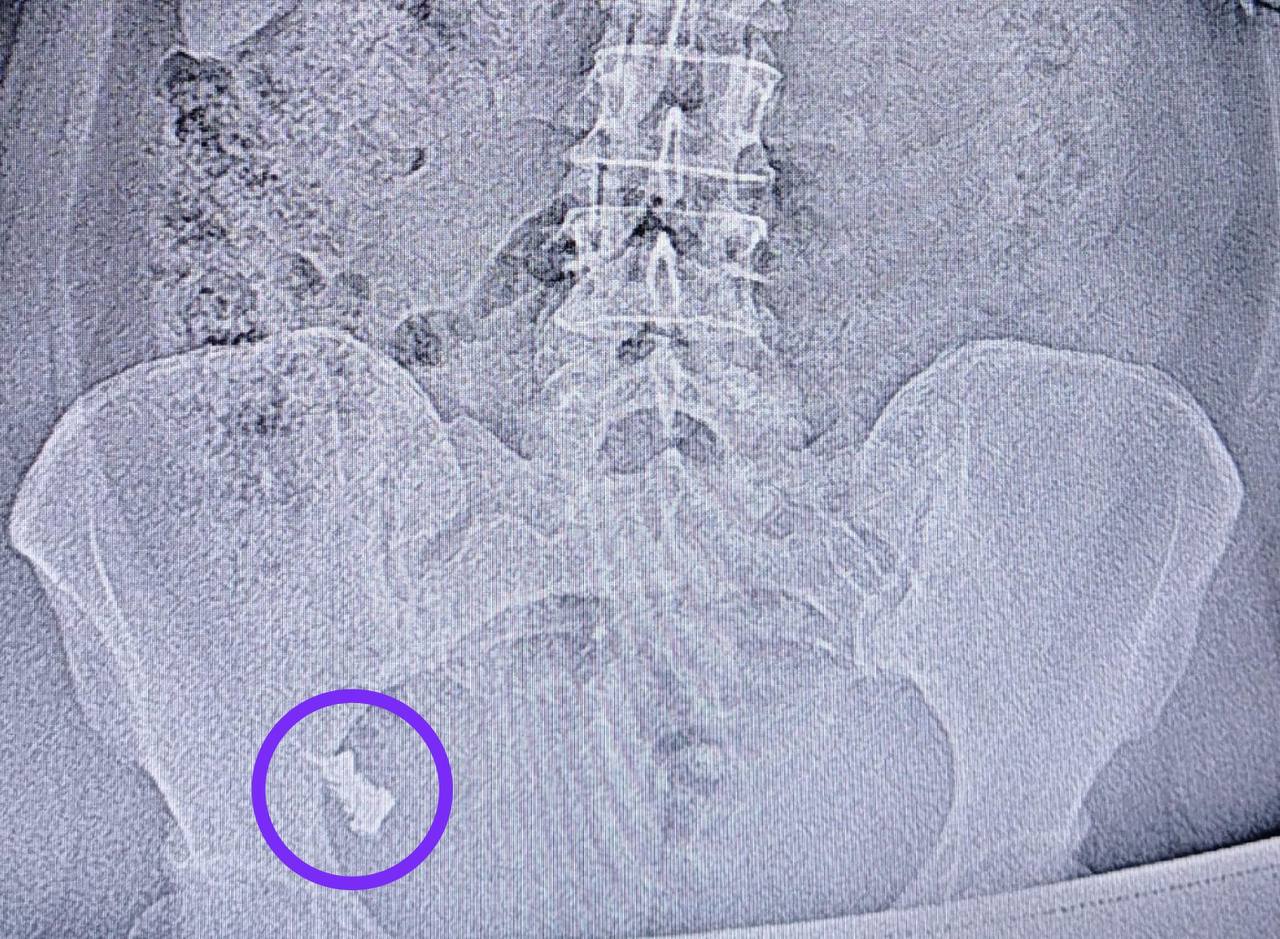

undefinedВ Казани врачи Республиканской клинической больницы извлекли зубной протез из кишечника 50-летней пациентки. Женщина случайно его проглотила, но долгое время отказывалась от госпитализации и ФГДС, надеясь, что инородное тело выйдет естественным путем.

Через неделю состояние ухудшилось, и пациентку всё же доставили в хирургическое отделение №1. Осмотр показал, что протез застрял в области перехода тонкой кишки в толстую.

Эндоскопист Наиль Исхаков во время колоноскопии смог извлечь протез. Процедура проходила под контролем анестезиолога-реаниматолога Елены Чуенковой. Благодаря наркозу операция прошла безболезненно и успешно.

Фото: РКБ Татарстана